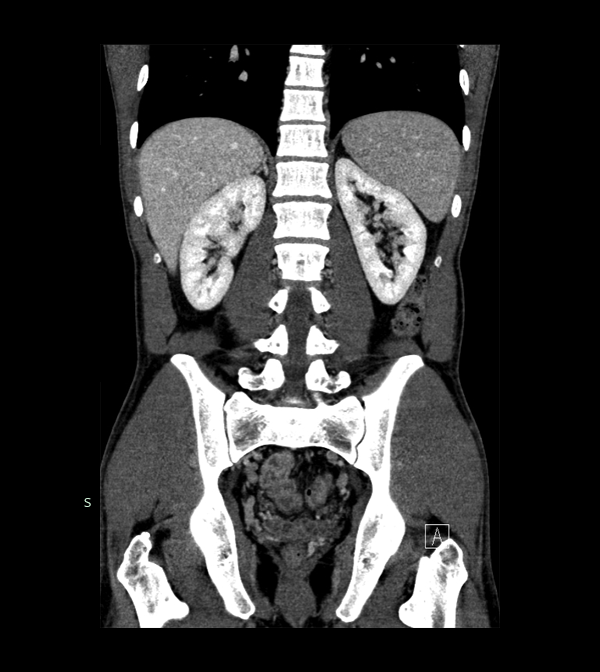

Body

Covers abdominal CT anatomy.